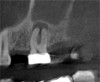

Three months after NSRCT and one month after FESS, she returned to her endodontist for a follow-up appointment. She reported experiencing only minor sinus pressure, which she believed to be attributed to seasonal allergies. Upon examination, no swelling, mobility, or sinus tracts were noted, and tooth No. 2 was not tender to percussion or palpation. CBCT imaging revealed both clearing of the sinus and initial healing of the apical pathosis (Figure 7 and Figure 8). Continued follow-up appointments were recommended.

(7.) Postoperative CBCT images taken 3 months after NSRCT (ie, 6 weeks after sinus surgery), showing sinus clearing and reduction in the size of the PAO lesion.

Figure 7

(8.) Postoperative CBCT images taken 3 months after NSRCT (ie, 6 weeks after sinus surgery), showing sinus clearing and reduction in the size of the PAO lesion.

Figure 8